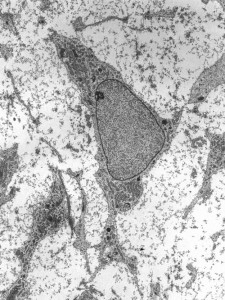

Stem cells are a unique group of biological cells that have the capability to self-renew and differentiate into different cell types. The field of regenerative medicine has delved into the science of repairing and replacing diseased tissues and organs through stem cell transplantation.

500px-msc_high_magnification

So, what does it have to do with plastic surgery? Regenerative medicine and plastic surgery share the basic principle of using a patient’s own tissue to restore and enhance the body. There are believed to be many advantages to stem cell use in plastic surgery including accelerated wound healing, reduced scarring, and increased fat graft survival. A very promising role for  stem cells is to grow tissues, such as bone and cartilage, that can then be used in the operating room to improve the outcome of surgical procedures. However, the stem cell hype that has been prevalent in recent years does not equate to proven, safe treatment strategies or outcomes with this technology. While the public is bombarded with exaggerated claims of innovative, stunning results and improved safety, many unassuming patients are being subjected to unregulated stem cell procedures. Until such time that adequate scientific and clinical evidence to promote more widespread use of stem cells in plastic surgery is published, patients should adhere to the old adage of “buyer beware”.